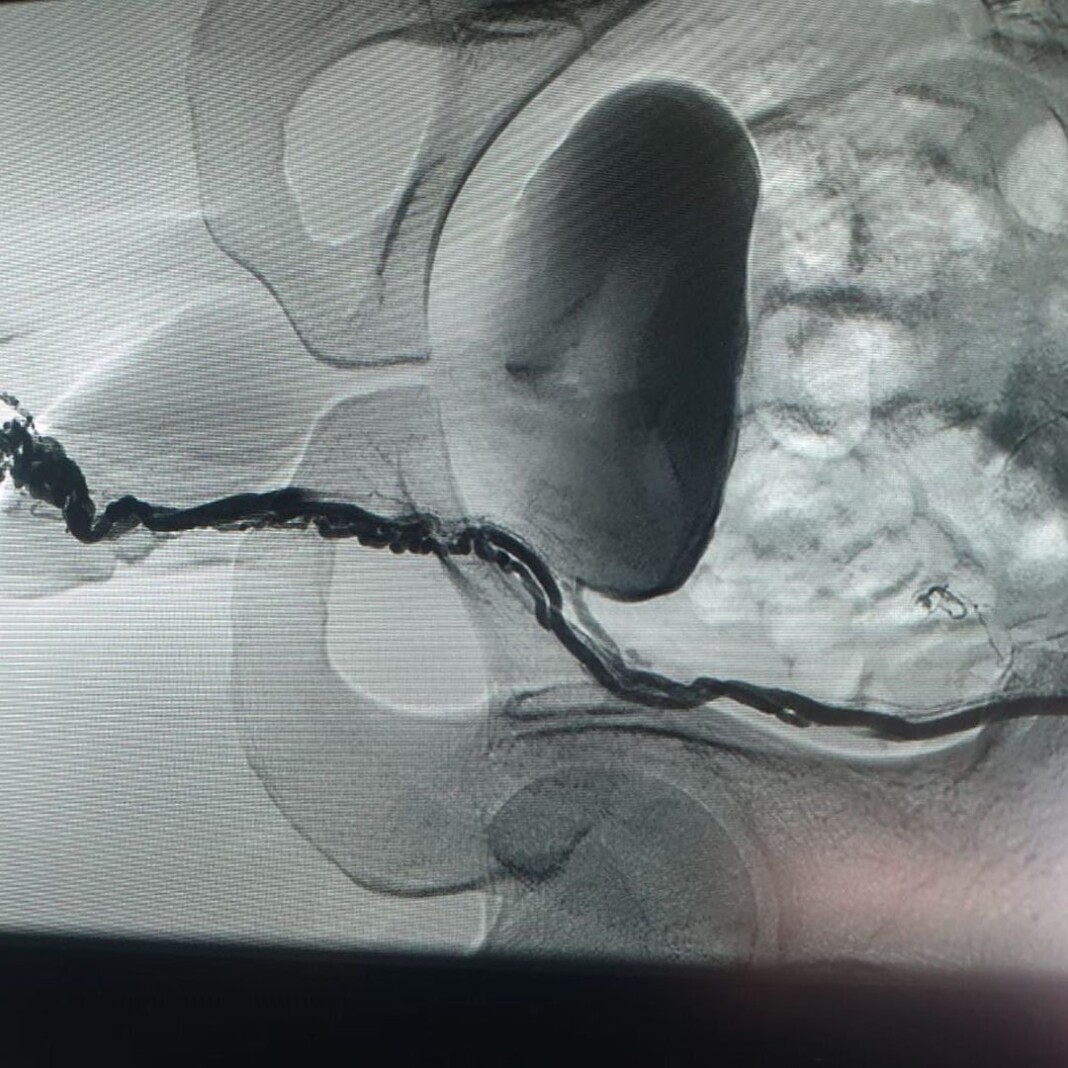

мболизация яичковой

Эмболизация яичковой 115 фото